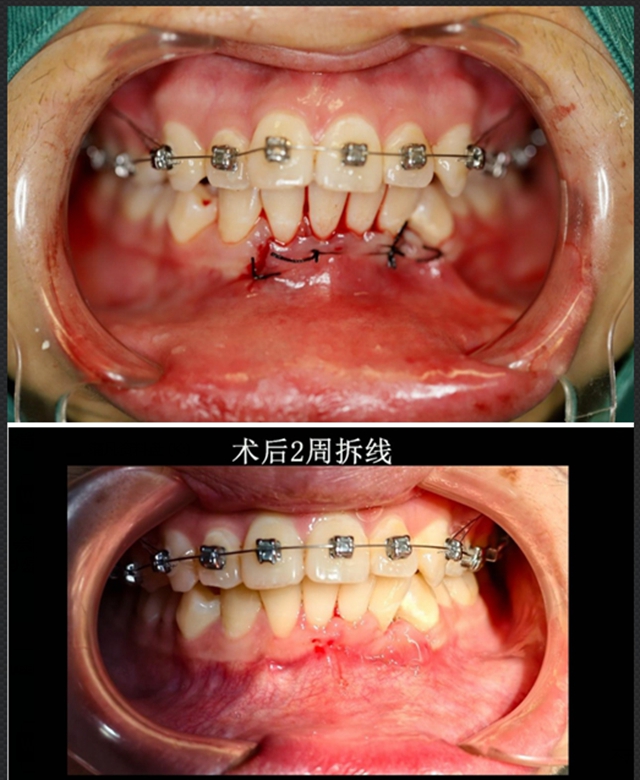

针对小陈情况,口腔诊疗中心立即开展了病例讨论,最终确定了“手术拔除+同期正畸规划”的个性化方案。

整个治疗过程就像一场精准的“排雷行动”,既要完成埋伏牙拔除,还要保证不损伤邻牙牙根及血管。

基于三维重建的结果,设计微创手术路径,避开重要解剖结构,拔除异位尖牙。

2周后拆线时,小陈伤口恢复非常理想,并未出现神经症状和其他不适。

目前小陈已进入正畸调整阶段,面部轮廓和咀嚼功能都有了显著改善。